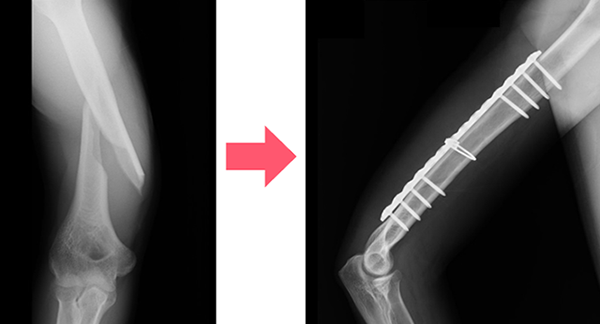

2. 手術治療

プレート固定や髄内釘(芯棒を入れる)固定などの手術療法があります。 どのような手術方法が良いかは骨折の場所や状態などを見て判断します。 粉砕骨折や軟部組織の損傷が激しい開放性骨折など、様々な理由ですぐにプレート固定や髄内釘固定手術が行えず、本番の手術までに待機期間を要する場合は、骨折部の上下に経皮的に骨にピンを刺入して体外でロッドを用いて連結させて骨折部を安定化させる創外固定という手術を応急的に行う場合もあります。手術は全身麻酔で行われることが多く入院が必要になります。

プレート固定